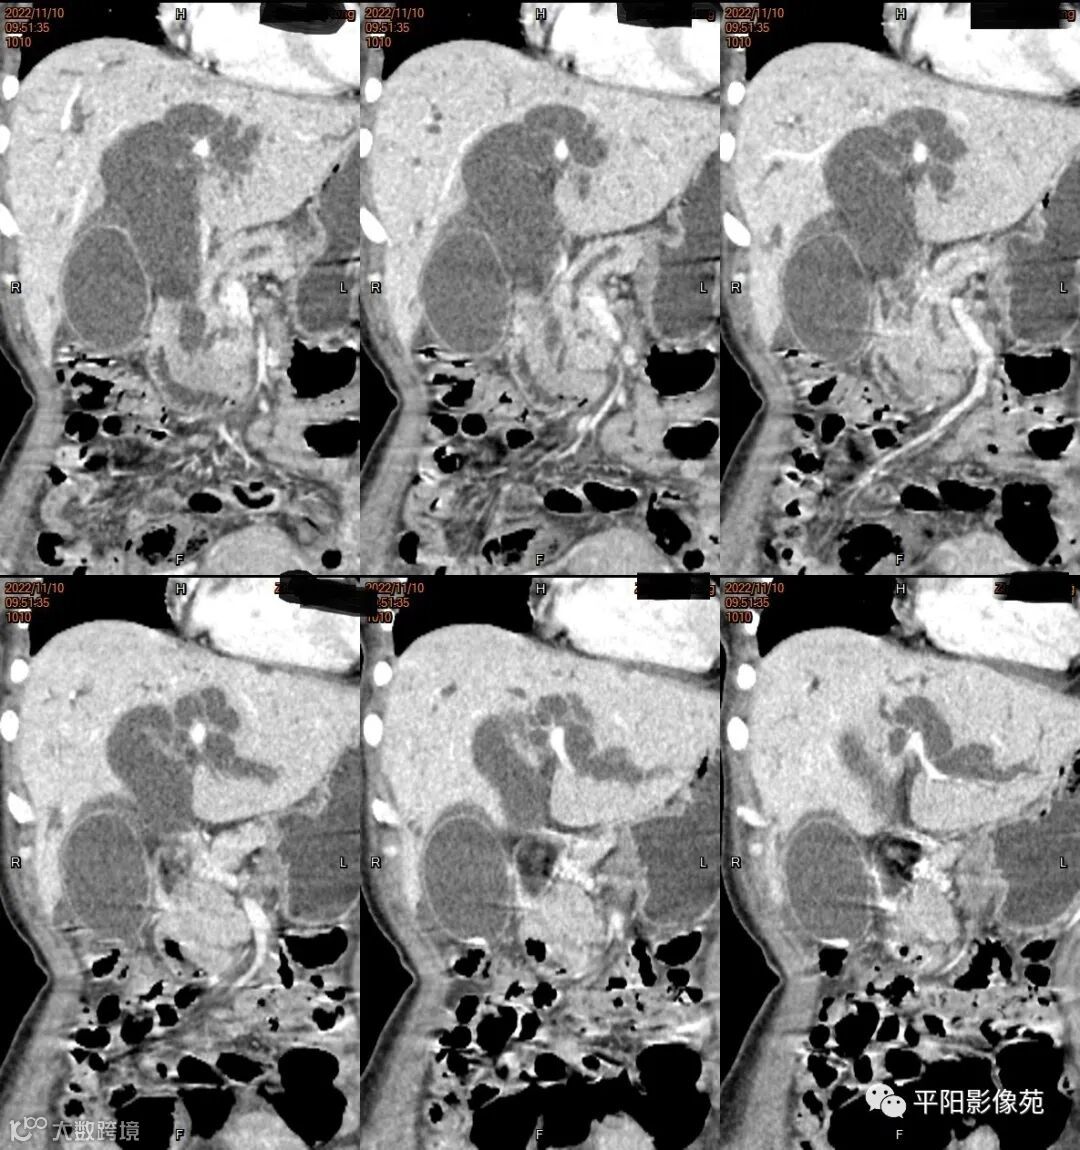

影像学检查

CT

影像表现: